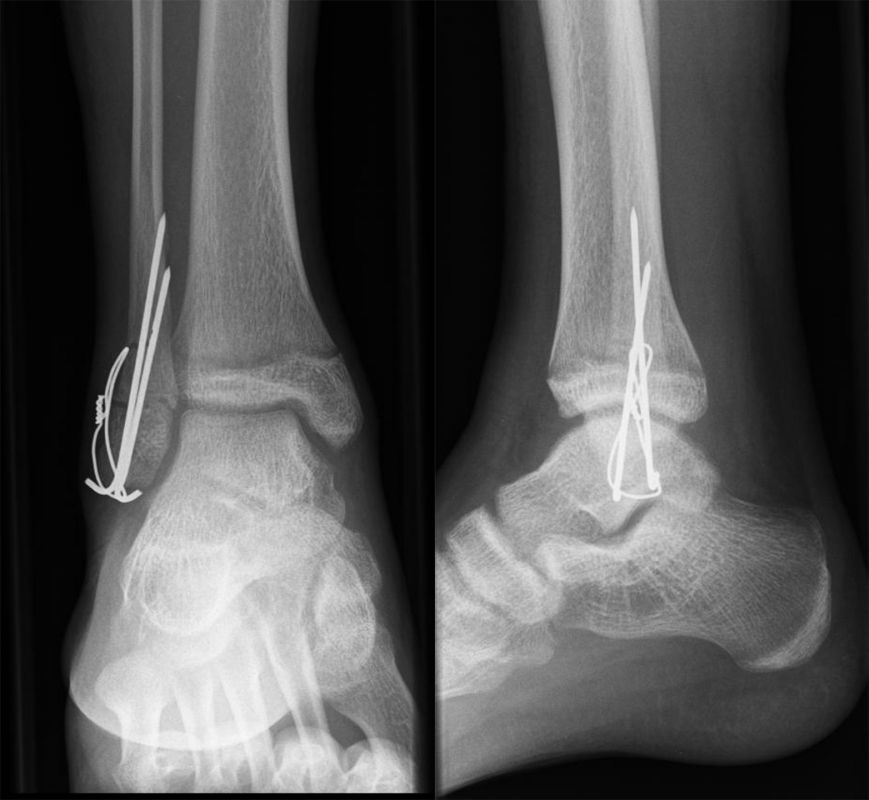

Fugengelenkfrakturen treten typischerweise vor dem 10. Lebensjahr auf, in einer Phase, in welcher die Wachstumsfugen noch weit offen sind. Dieser Frakturtyp betrifft fast ausschließlich den medialen Malleolus. Laterale Frakturen sind extrem selten, teilweise kommt es zu lateralen Bandverletzungen oder Fugenschaftfrakturen der distalen Fibula. Die Frakturlinie verläuft in einer Verlängerungslinie von der medialen Taluskante nach proximal. Häufig stellen sich Verletzungen des Innenknöchels im Röntgenbild schlechter dar, insbesondere wenn die Aufnahmen verdreht sind oder die Ebene der Fraktur bei geringer Dislokation verkippt zur Röntgenebene liegt. Besteht klinisch der geringste Hinweis auf eine Verletzung des Innenknöchels, muss aufgrund der Tragweite der Verletzung durch entsprechende Aufnahmen gegebenenfalls auch Schnittbildverfahren die Verletzung sicher diagnostiziert oder ausgeschlossen werden (Abb. 15).

„Kadiläsion“- Mediale Malleolarfraktur

Bei kindlichen Verletzungen des medialen Malleolus handelt es sich nach L. v. Laer um eine sogenannte Kadiläsion, d.h. eine Verletzung mit hohem Risiko eines schlechten Behandlungsergebnisses bei nicht korrekter Behandlung. Selbst bei optimaler Therapie ist das Risiko für spätere Wachstumsstörungen hoch, sodass diese Verletzungen nicht selten ein juristisches Nachspiel haben. Durch die Verletzung der wachstumsaktiven Zone kann es zu einem vorzeitigen Verschluss der Wachstumsfuge kommen, mit entsprechendem Fehlwachstum. Das Risiko eines vorzeitigen Verschlusses der Wachstumsfuge korreliert mit dem Ausmaß der Schädigung der wachstumsaktiven Zone. Ab dem 13. Lebensjahr wird das Risiko bei reduzierter Wachstumsaktivität zunehmend geringer.

Fugengelenkfrakturen können die Wachstumsfuge durchkreuzen (Abbildung 16a), ohne oder nur mit minimaler Beteiligung der Fuge sehr weit medial liegen (Abbildung 16b) oder durch die Fuge auslaufen (Abbildung 16c). Relevant für die Wachstumsprognose ist weniger die Form der Fraktur, sondern das Alter des Patienten zum Zeitpunkt des Traumas sowie das Ausmaß der Schädigung der Wachstumsfuge, wobei eine Korrelation mit dem Ausmaß der Dislokation besteht.

THERAPIE

Behandlungsziel ist die exakte Rekonstruktion der Gelenkfläche sowie die Minimierung des Risikos einer späteren Wachstumsstörung. Dislozierte Frakturen werden offen reponiert, die Osteosynthese erfolgt mit einer Kleinfragmentschraube. Finden sich viele kleine Fragmente kann eine K-Draht Osteosynthese durchgeführt werden. Wird der Innenknöchel operiert, kann bei gleichzeitiger hochgradiger lateraler Instabilität eine Rekonstruktion des lateralen Bandapparats durchgeführt werden. Fibula Frakturen stellen sich meist spontan ein, sodass hier keine zusätzliche Osteosynthese notwendig ist.

Nach der Osteosynthese wird die Fraktur für ca. vier Wochen in einem Unterschenkelgips ruhiggestellt. Bei Schmerzfreiheit der Frakturzone erfolgt anschließend eine schmerzadaptierte Belastungssteigerung über weitere zwei Wochen. Sobald unter Alltagsbedingungen Beschwerdefreiheit besteht kann die sportliche Belastung langsam gesteigert werden. Kirschnerdrähte werden 6-8 Wochen postoperativ, Schrauben nach zwölf Wochen entfernt. Es empfiehlt sich klinische und radiologische Kontrollen im Abstand von 6 Monaten bis zum Wachstumsabschluss durchzuführen, um ein mögliches Fehlwachstum frühzeitig zu erkennen.